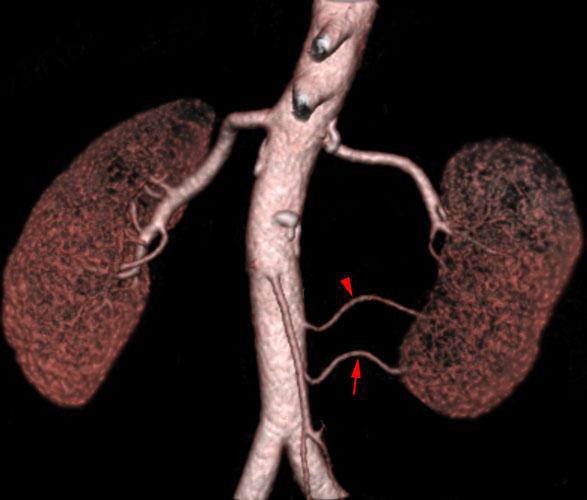

Arterias renales accesorias